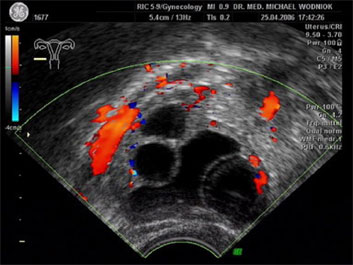

Hochauflösende Ultraschalluntersuchungen in Kombination mit der 3D-4D Technik werden in unserer Praxis routinemäßig durchgeführt. Dabei werden im Rahmen der Vorsorgeuntersuchung, sowie bei reinen vorsorglichen Ultraschalluntersuchungen auf Wunsch, auffällige Tastbefunde und noch unentdeckte Befunde weiter sonografisch abgeklärt. Bei zweifelhaften Befunden der Brüstdrüsen oder von Organen der inneren Genitalien kann der zusätzliche Einsatz der Farbdopplertechnik sehr hilfreich sein. Dabei stellt diese Technik bildlich sehr genau den Blutfluss, die Flussgeschwindigkeit, den Blutflusswiderstand sowie die Blutflussrichtung aller Blutgefässe dar. Die Interpretation dieser Ergebnisse fließt als zusätzlicher „Marker“ in die Entscheidung für das weitere klinische Vorgehen ein. Ein zunächst als völlig unauffällig eingestufter Ultraschallbefund eines zystischen Befundes im Eierstock wird bei einem unerwartet auffälligen Blutfluss an der inneren Zystenwand eine zeitnahe weitere Abklärung zu Folge haben. ![]() ![]() ![]()